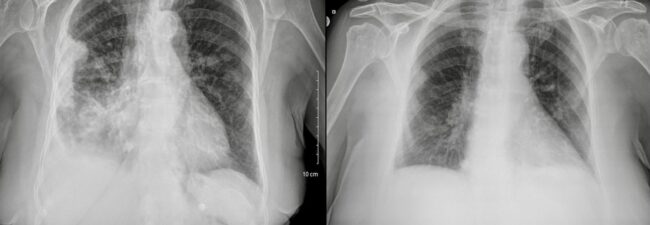

Introduction Recurrent pleural effusions (RPEs) are defined as pleural effusions that recur despite optimal therapy for the underlying etiology of the effusions and typically require multiple thoracenteses or a more definitive therapeutic modality to prevent a recurrence. Indwelling pleural catheters (IPCs) have emerged in the past decade as a very effective modality to treat and…